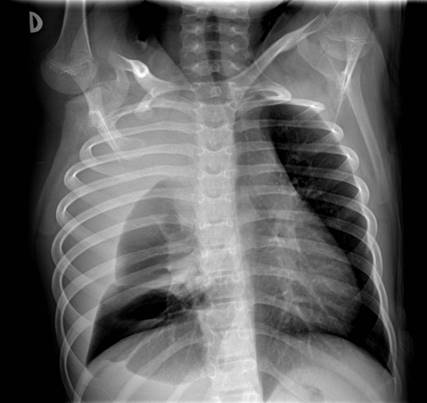

Dada la clínica se decide realizar radiografía de tórax (Figura 1) en la que se identifica derrame pleural derecho y una masa en segmento anterior del lóbulo superior derecho (LSD) con una lesión lítica expansiva en el segundo arco costal anterior derecho. Se amplia estudio con ecografía en la que se visualiza una masa pleural / pulmonar en segmento anterior de LSD con probable afectación mediastínica, derrame pleural derecho y alteración en la cortical del segundo arco costal anterior derecho. Se decide realizar TC torácico con contraste (Figura 2), (Figura 3) y (Figura 4) para valorar extensión y características de la lesión, identificándose una masa de aproximadamente 120x130x100 mm que ocupa casi todo el hemitórax derecho, heterogénea, con múltiples áreas quístico-necróticas en su interior. Condiciona desviación contralateral del mediastino y su infiltración, comprimiendo la vena cava inferior, sin claro plano de separación y contactando con el pericardio con signos de infiltración de la aurícula derecha. Comprime el bronquio principal derecho y sus ramas, condicionando atelectasia parcial secundaria y contacta con el segmento extrapericárdico de la arteria pulmonar derecha y ambas venas pulmonares derechas.

Figura 1: Derrame pleural derecho y una masa en segmento anterior de LSD con una lesión lítica expansiva en el segundo arco costal anterior derecho.